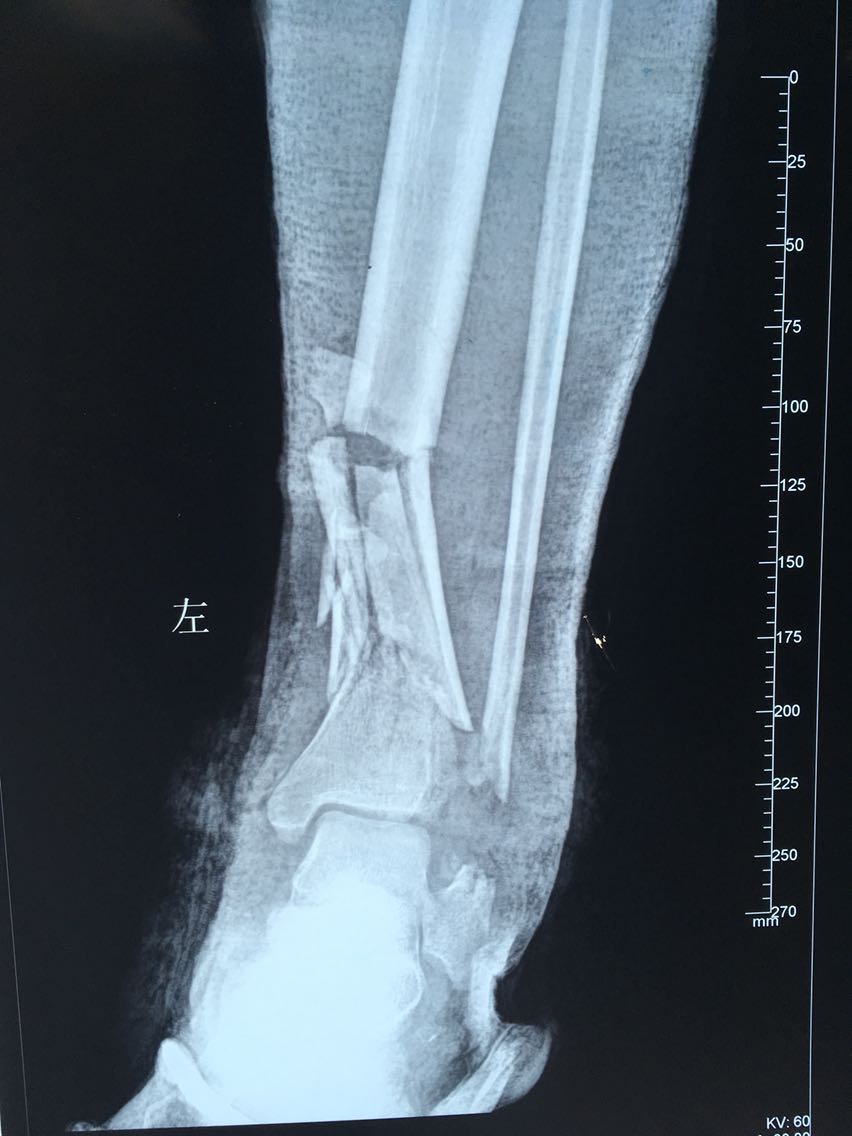

查体:左下肢肿胀,腓骨下段外侧皮肤、足背外侧皮肤碾挫严重,外踝部骨质外露,左小腿下段可触及骨擦感,出现反常活动,足背动脉可触及,左下肢皮肤感觉过敏,皮温略低,末梢毛细血管充盈未见明显异常。 辅查:左胫腓骨远端骨质碎裂,骨折端移位,骨折线波及胫距关节面,下胫腓关节间隙消失;左跟骨、骰骨骨质碎裂,骨折块移位,跟骰关节受累。

诊断:车祸伤:1.左胫腓骨远端开放性粉碎性骨折2.左跟骨开放性粉碎性骨折3.左骰骨粉碎性骨折 治疗:急行清创探查骨折复位外固定架固定治疗。